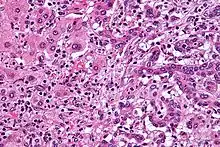

- ... that rare mistargetting of somatic hypermutation is being investigated as a mechanism in the development of B-cell lymphomas?